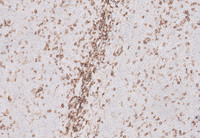

Figure 5: CD20 in Splenic Marginal Zone Lymphoma

The lymphoma nodules are strongly positive for CD20, confirming B-cell origin. Also, on CD20, increased numbers of lymphoma cells infiltrating the red pulp are also noted.